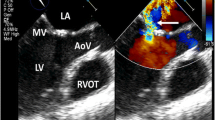

Valvular disease

Mediastinal radiation frequently causes valvular heart disease. In a postmortem study, radiation-related valvular disease was identified in 71 % of patients in whom valves were available [15]. In this study, the aortic valve was most commonly affected, followed by the mitral and tricuspid valves, respectively. More than one valve can be involved and valvular disease often occurs in conjunction with other cardiac complications [34]. The spectrum of radiation-induced valvular disease can range from endocardial thickening without functional abnormality, to asymptomatic valvular dysfunction, and eventually to symptomatic valvular stenosis or regurgitation. Asymptomatic thickening is the most common manifestation of radiation-induced valvular disease. When significant, combined aortic regurgitation and stenosis are the most common findings, with mitral regurgitation following in incidence [35].

Cardiac auscultation for detection of murmurs is a simple first line screening method to detect asymptomatic valvular dysfunction. However, the diagnostic yield of cardiac auscultation is poor. Transthoracic echocardiography is a safe and cost effective imaging tool for the detection of radiation-induced valvular heart disease. It also permits evaluation for asymptomatic Stage B heart disease and therefore it is recommended that screening echocardiography be performed periodically, based on the radiation exposure and/or anthracycline therapy. The exact interval at which these surveillance echocardiograms should be performed remains a matter of significant debate and controversy.